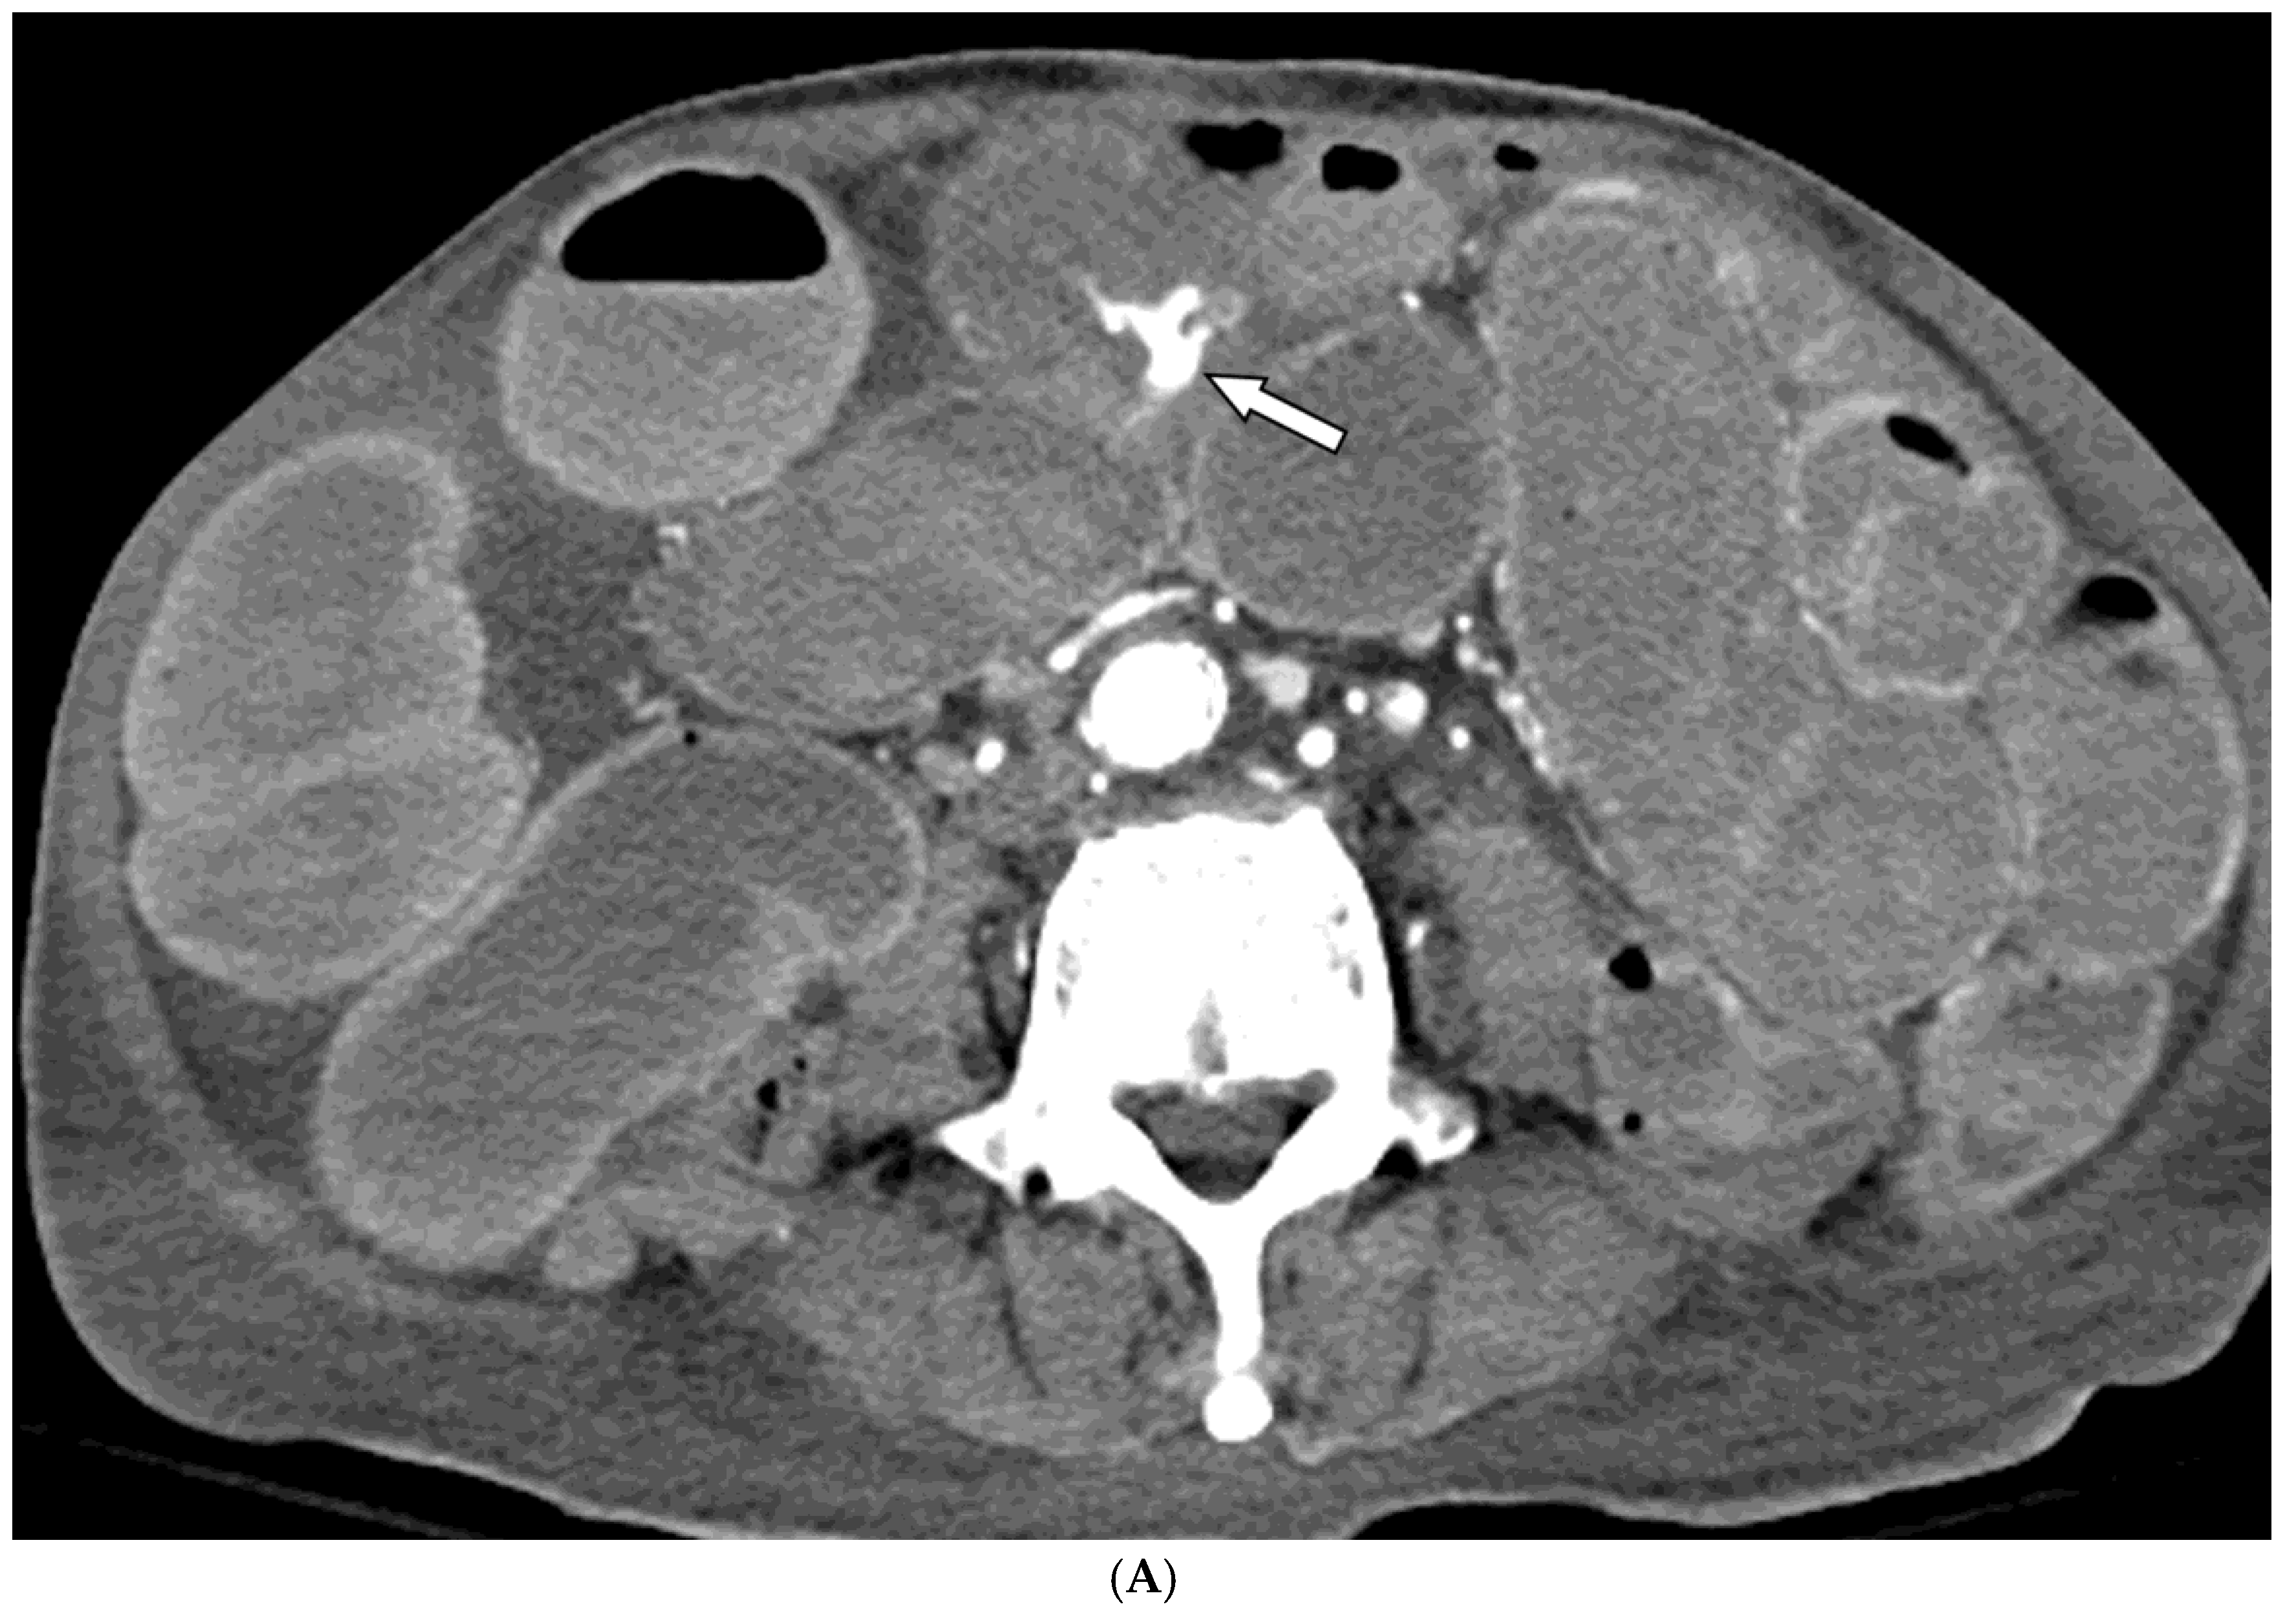

Figure 1. A 78-year-old man presented with hematochezia. (A) Contrast-enhanced axial CT image shows luminal contrast extravasation (arrow) at the ileal loop. (B, C) Selective ileal arteriography shows contrast extravasation (arrows). Due to the distance and tortuosity of the path from the microcatheter tip (arrowheads) to the bleeding focus, superselection was not possible; therefore, embolization was performed using quick-soluble gelatin sponge particles (350–560 µm). (D) Post-embolization arteriography demonstrates that the bleeding focus and the arterial branches leading to it are no longer visible. No further bleeding occurred during the 1-year follow-up.